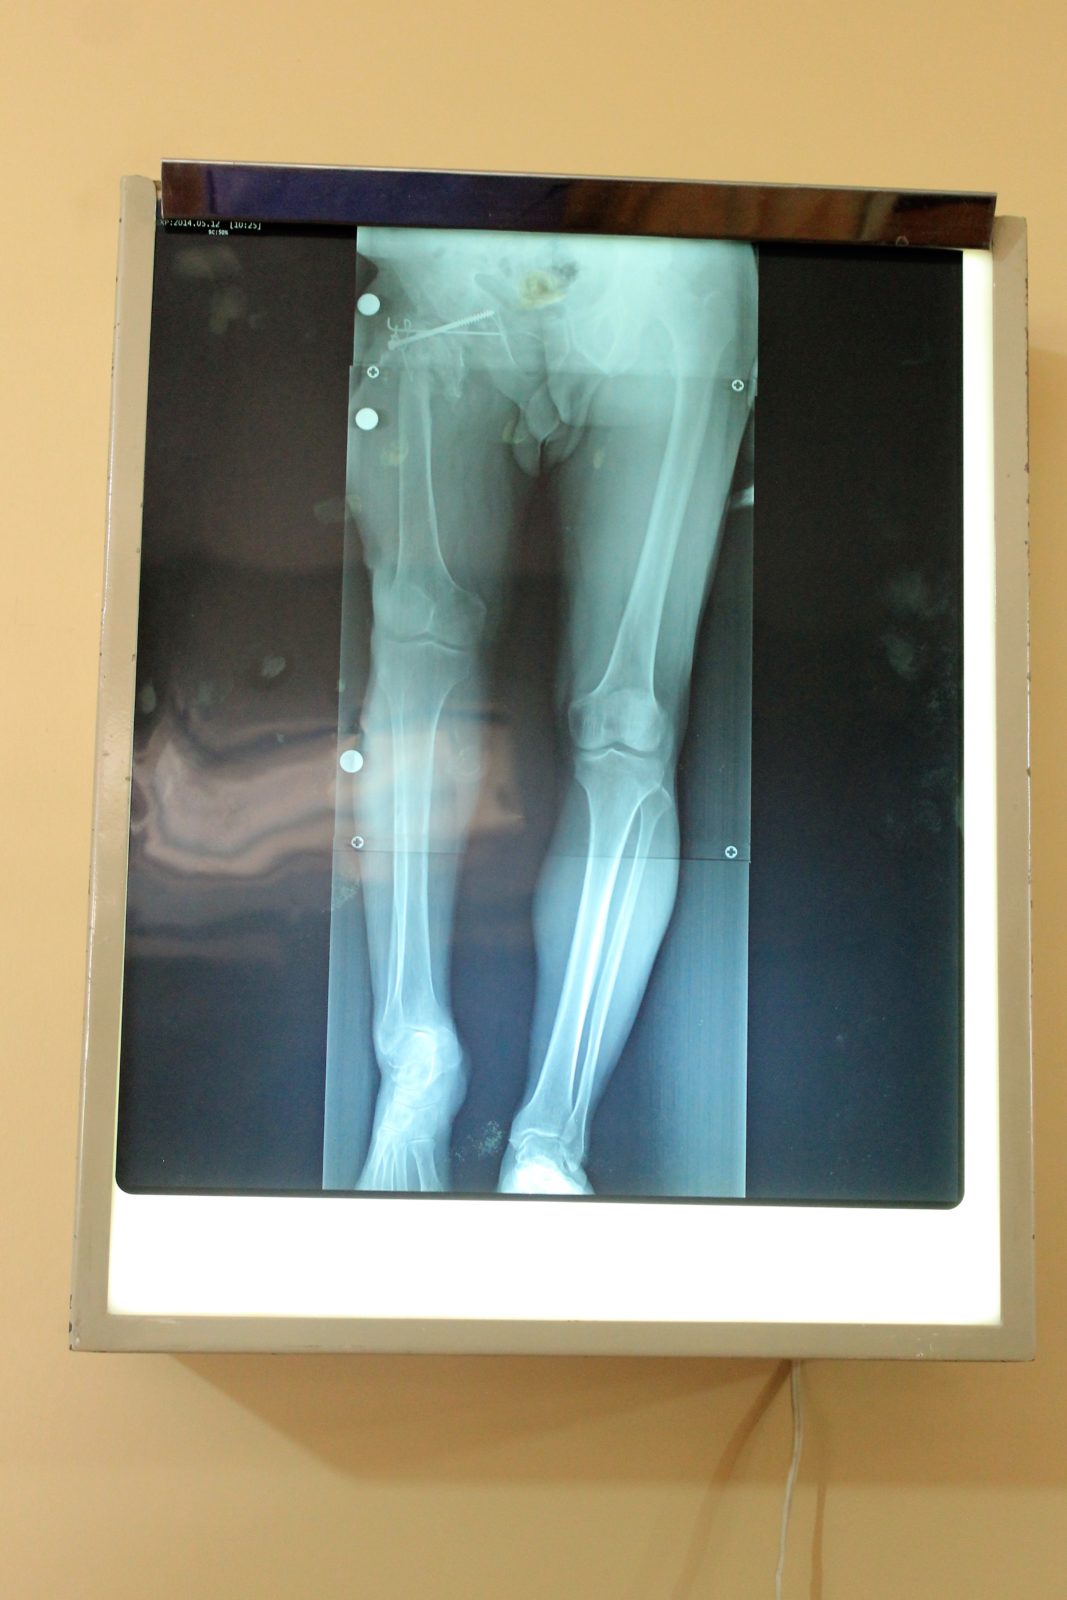

That process was put into motion at the clinic where TNMS’s doctors, nurses, physiotherapists, joint replacement specialists and general volunteers evaluated over 40 patients to assess viability for surgery this week. When we arrived today at the clinic, most of these patients were waiting outside, and were very happy to see our team (just as we were happy to see them!). Every team member worked especially hard today as we funnelled each patient, one by one, in to see the doctors. Those team members able to translate were in high demand all day, and did incredible work today as they were pulled in several directions by doctors, nurses and volunteers needing to communicate with our patients. The experience was inspiring and, at the same time, deflating, as we all felt the excitement for those who were to receive promising life changing surgery and disappointment for those who were not candidates for surgical help (for various medical reasons). All went smoothly and 28 patients were booked for surgery (3 on the waiting list in case of cancellations).